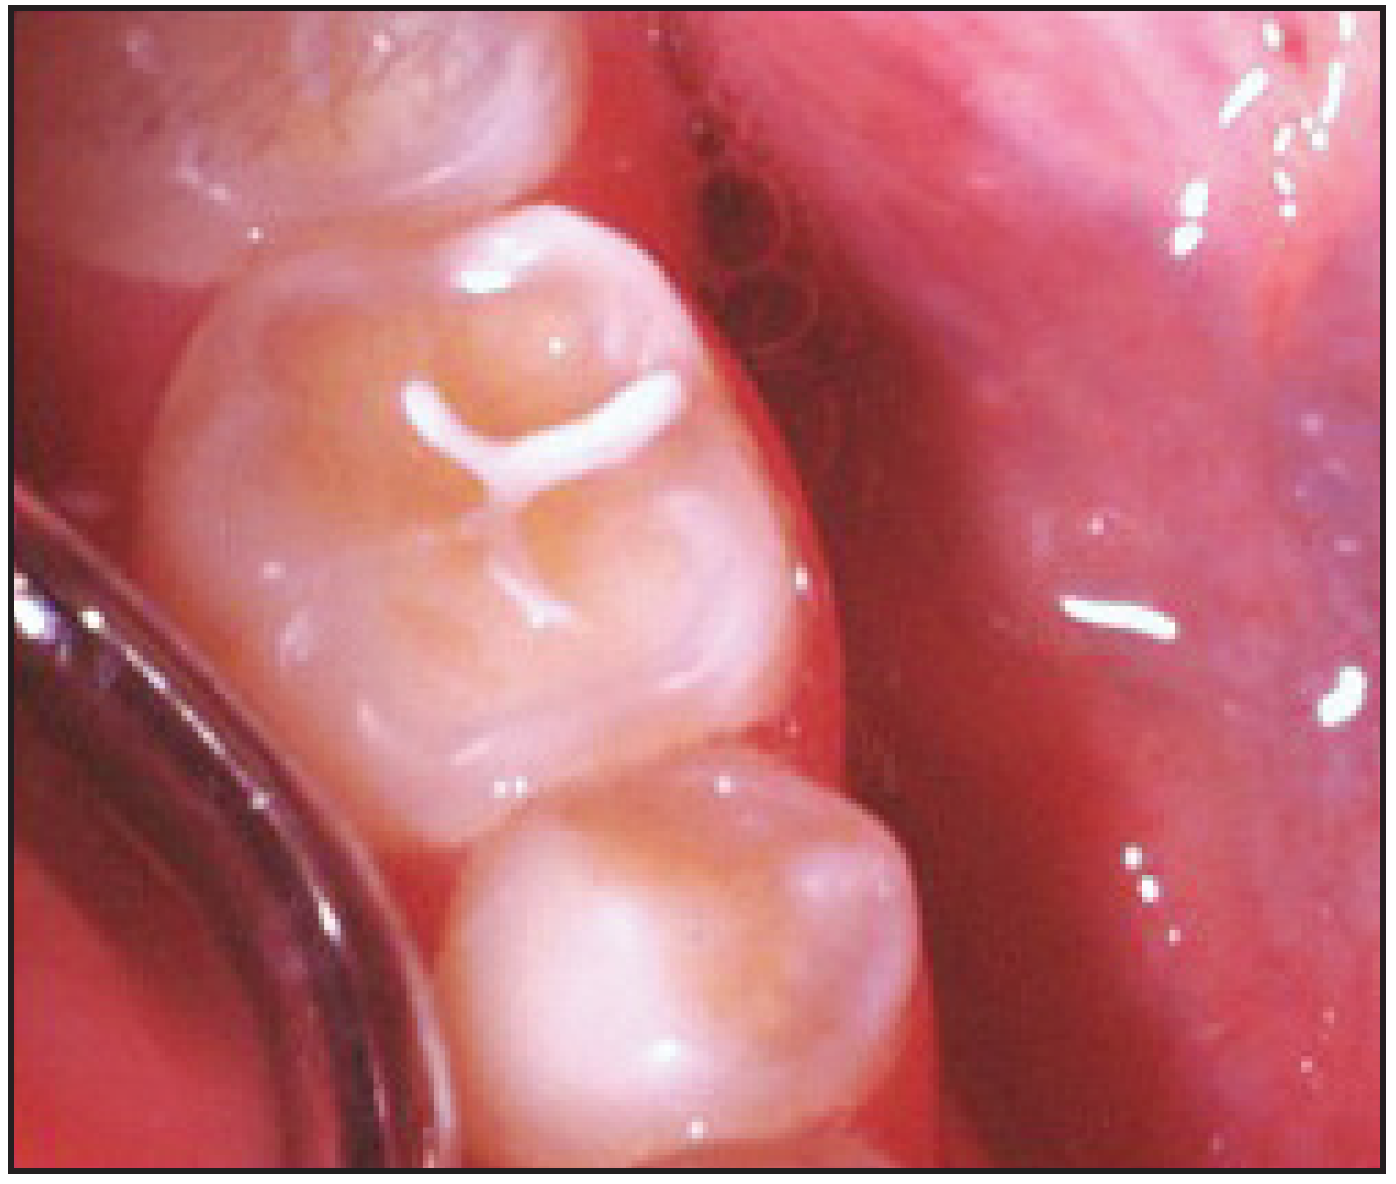

Recognizing the Signs of Soda Pop Erosion

Patients with soda pop erosion present with certain changes in the morphology and surface characteristics of their teeth. Smooth surface enamel may develop broad, shiny concavities. The teeth may even have a glazed appearance.23 Mandibular premolars and molars commonly develop wide concavities on their buccal surfaces in the cervical third. These concavities may terminate at the free gingival margin, producing a characteristic enamel cuff at the free gingival margin, or they may extend on to the root surface if the roots are exposed. The occlusal surfaces of premolars and molars may be punctuated by deep, shiny concavities that may extend down into the dentin. The occlusal surfaces that have been partially restored may demonstrate loss of enamel around the occlusal aspect of the restoration so that it appears to rise above the existing occlusal surface. These features can be seen in Figure 5 and Figure 6. The maxillary central incisors may appear thinner with an increase in incisal translucency. The surface will appear polished and smooth, and distinctive surface characteristics will be missing. Erosion of the occlusal surface of permanent first molars with sealants may result in the sealants appearing to rise above the occlusal surface. Erosion from soda pop in the primary dentition will show as a loss of surface definition and detail. The enamel and dentin layers are much thinner than in the permanent dentition and there is an increased chance of erosion leading to pulp exposure.24 (Table 2)

Figure 5 – Concavities on Buccal Surface of Eroded Teeth.<sup>25</sup>

Figure 5

Figure 6 – Erosion. Courtesy of Dr. Peter Endo.

Figure 6